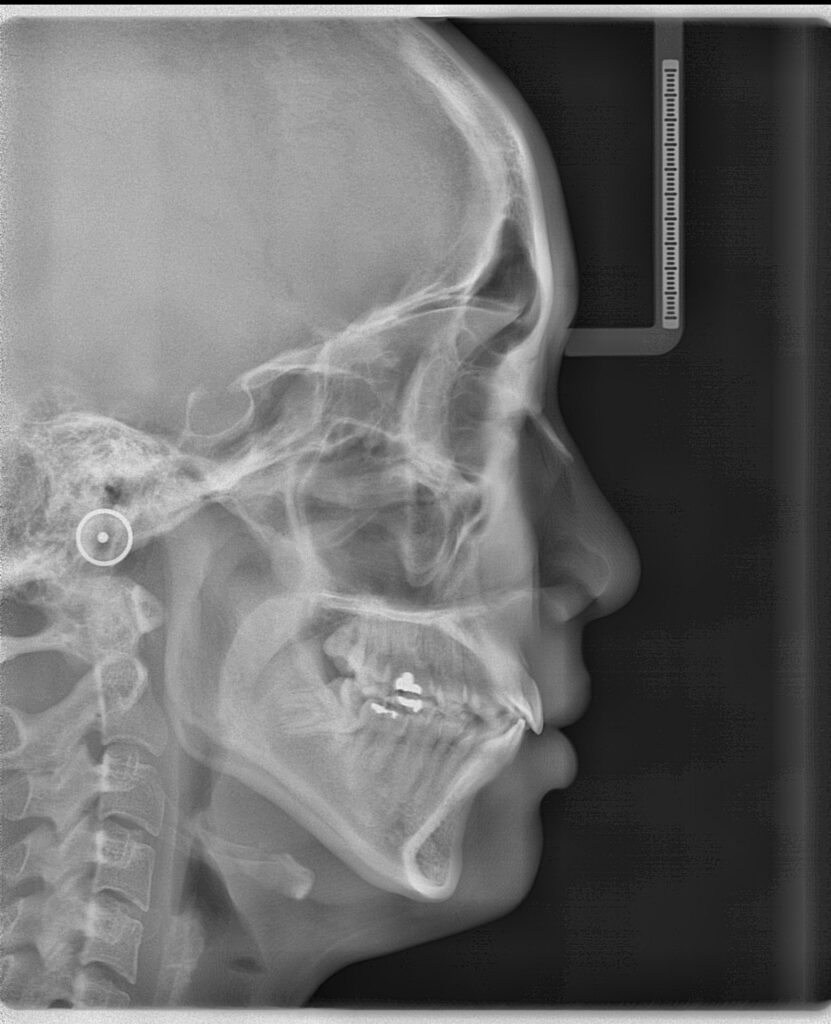

Cephalometric X-ray

เป็นภาพถ่ายด้านข้างศรีษะ ใช้ในการประเมินความสัมพันธ์ของฟันและโครงสร้างใบหน้า, โดยเฉพาะในการวางแผนการจัดฟัน